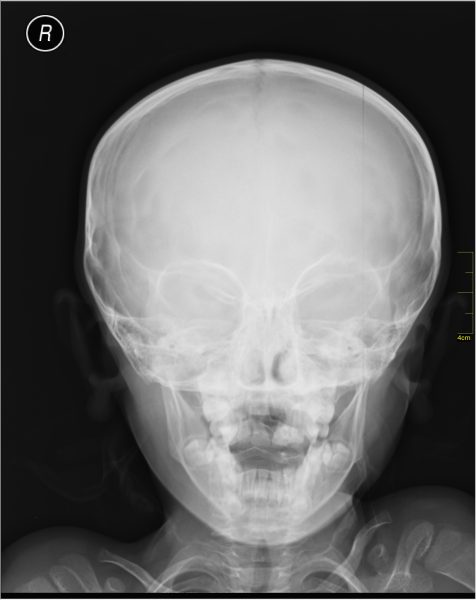

In a hospital, X‑ray imaging works a bit like shadow theatre. An X‑ray beam is sent through the body onto a detector. Soft tissue lets more X‑rays through, while bones absorb more. The detector records these differences, and the result is an image where bones appear bright and soft tissue appears darker.[6] The picture is created mainly by absorption, i.e. how much X‑ray intensity is lost on the way through.

This method is quick and extremely useful in the field of medicine, but it does have its limitations. A shadow image tells you that “something blocks X‑rays here”, not exactly how atoms are arranged. To reveal tiny structures, such as the shape of a protein, you need a different strategy.